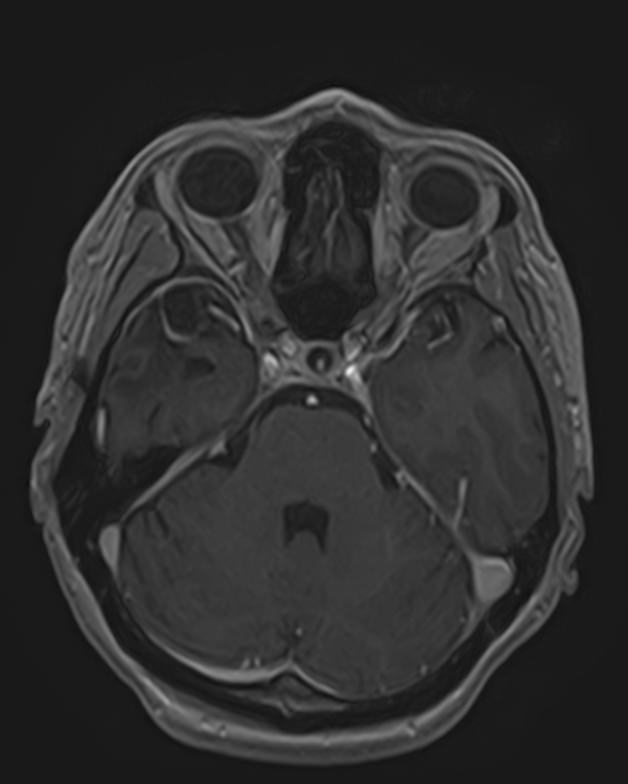

МРТ головного мозга с контрастированием – методика проведения магнитно-резонансной томографии, при которой внутривенно вводится препарат, содержащий гадодиамид (соли металла гадолиния). Контрастное вещество не проникает через гемато-энцефалический барьер и в норме не накапливается в тканях головного мозга. Однако при нарушении его целостности способно накапливаться в патологических очагах, в частности, в опухолях, зонах воспаления и участках демиелинизации нервных волокон.

Это способствует ранней диагностике заболеваний головного мозга, таких как рассеянный склероз, доброкачественные и злокачественные новообразования. Кроме того, с помощью контраста можно оценить степень и характер васкуляризации патологического процесса.

Исследование в нашей клинике выполняется на современном высокопольном томографе экспертного класса TOSHIBA VANTAGE TITAN 1,5 Тесла, который использует разные режимы сканирования с толщиной среза от 1мм в различных плоскостях с последующей цифровой обработкой полученных данных для создания трехмерных изображений. Аппарат позволяет выявлять структурные изменения в веществе головного мозга уже на начальной стадии, когда другие методы не дают результатов.